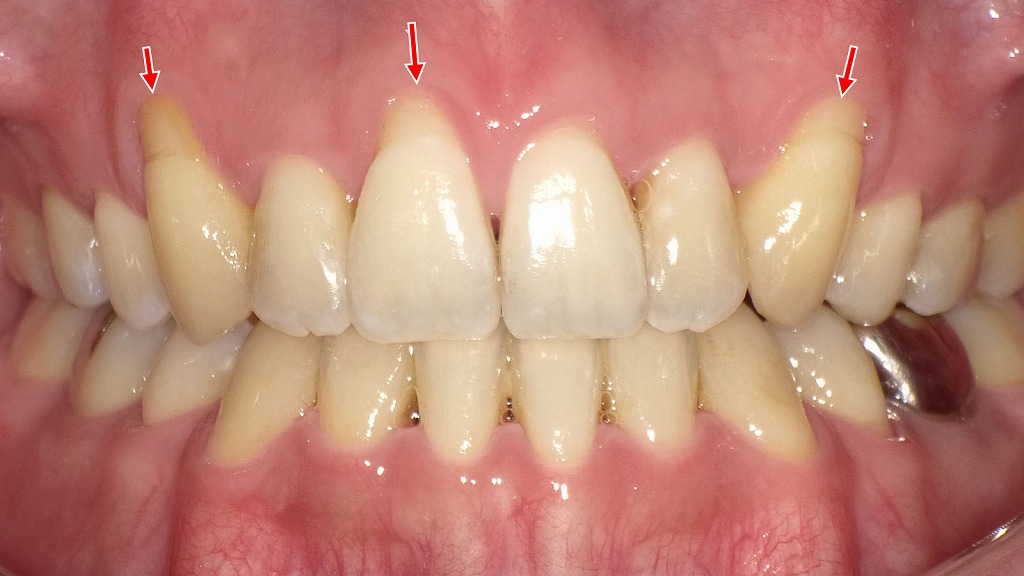

僅かな歯根露出があり凍みた症例

◆1枚目:ホワイトニング前の状態(僅かな歯根露出あり)

①歯の色調

- 全体的にやや黄ばみがあり、経年的な着色(ステイン)が認められます。

- 下顎前歯の表面に茶色い縦方向のステインが目立ちます。

②歯根の露出(矢印部)

- 矢印で示した大臼歯・小臼歯の根元に、わずかな歯肉退縮による歯根露出が確認できます。

- この段階では、「しみ」は軽度〜ほぼ無い程度と推測されます。

③歯肉の状態

- 全体として炎症はさほど強くないものの、部分的にやや歯肉が下がっており、長期的なブラッシング圧・加齢・咬合性外傷などの影響が考えられます。